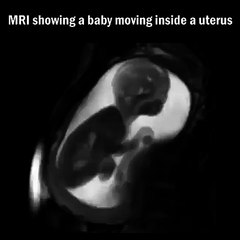

Ce bébé s’agite lorsque sa maman entre dans sa chambre